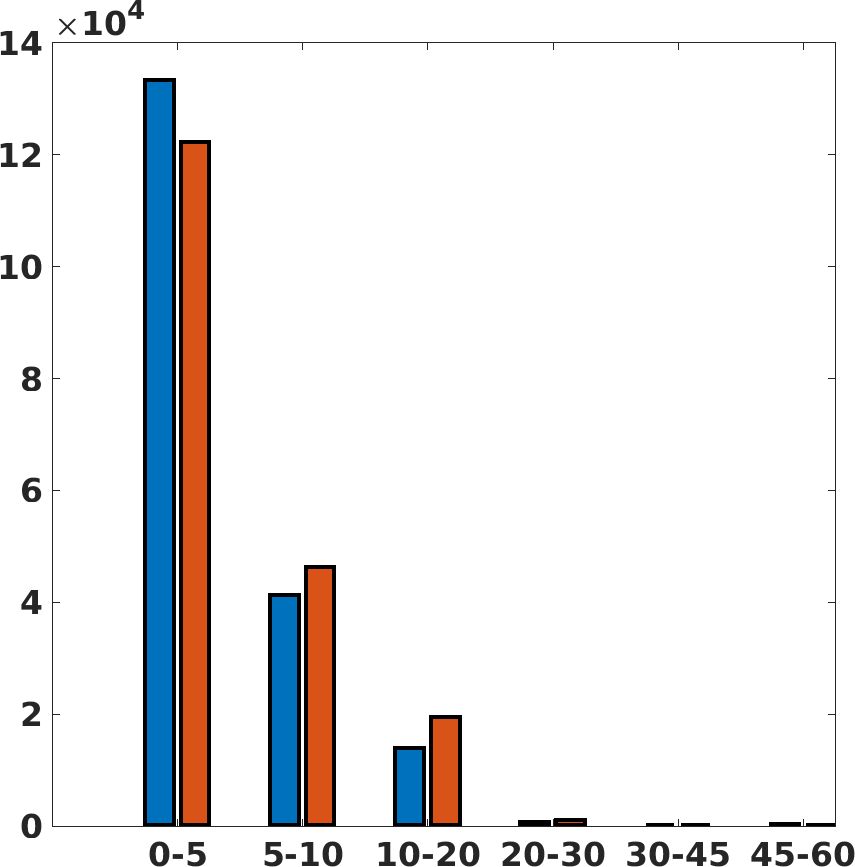

Fig. 7(a-b-c, left) shows the box plot of the statistics of the PSNR on three different anatomical districts, comparing the target images with the prediction and the cubic convolution, respectively. The metrics are computed on a data set of 200 images of the same district and with the same up-sampling factor. We report that the PSNR median value improves of on obstetric 2X raw images, on cardiac 2X raw images, and on abdominal raw 4X images.

Fig. 7(a-b-c, right) shows the histogram of the absolute value of the error with respect to the target image, of the prediction and Cubic convolution results, respectively. The histograms show the number of pixels where the prediction error is lower than 5 (i.e., the first bin of the histogram), which means very similar to the target when visually analysing the images. From the Cubic convolution to the predicted images, this value increases of on obstetric 4X raw images, on cardiac 4X raw images, and on abdominal 4X raw images.